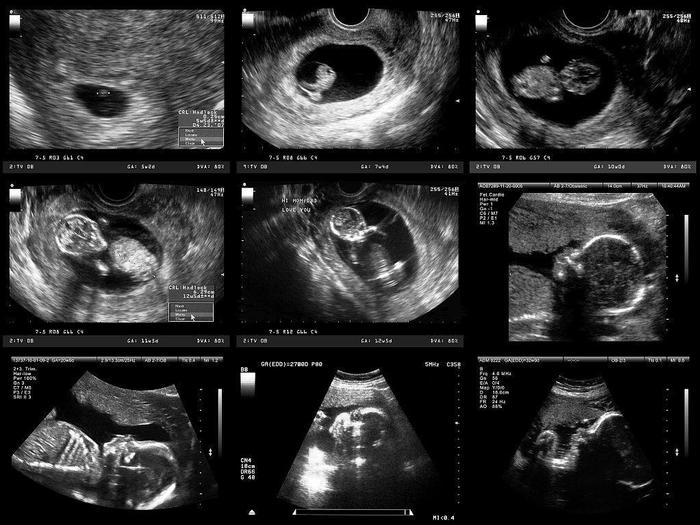

怀孕早期是胎儿细胞分裂期,当胚胎着床后就开始大脑的发育,这时受精卵不断地分裂,一部分形成大脑,另一部分形成神经组织。如果这个阶段的营养素缺乏,可能会使胎儿脑细胞的分裂期缩短,从而直接影响脑细胞的数量。而在怀孕的中期与晚期,是胎儿脑细胞的增殖期和肥大期。